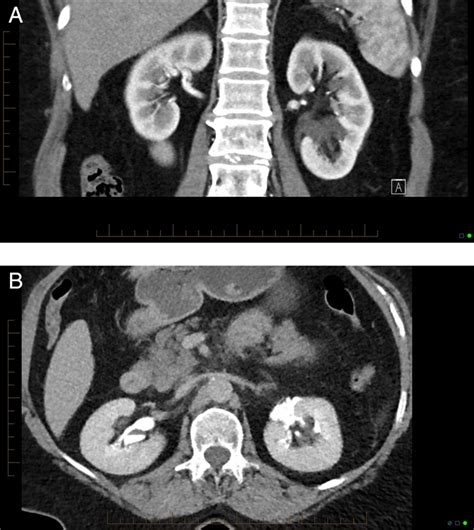

Understanding the intricacies of a CT Scan IVP (Computed Tomography Intravenous Pyelogram) is crucial for both medical professionals and patients. This diagnostic procedure combines the power of computed tomography (CT) with intravenous contrast to provide detailed images of the urinary system. By injecting a contrast dye into the bloodstream, the CT scan can highlight the kidneys, ureters, and bladder, making it easier to detect abnormalities such as stones, tumors, or blockages.

A CT Scan IVP is a specialized imaging technique that uses X-rays and computer technology to create detailed cross-sectional images of the body. The intravenous contrast dye enhances the visibility of the urinary system, allowing radiologists to identify issues that might not be apparent with standard X-rays or other imaging methods. This procedure is particularly useful for diagnosing conditions affecting the kidneys, ureters, and bladder.

After the CT Scan IVP, the radiologist will review the images to identify any abnormalities in the urinary system. The results are typically available within a few hours to a few days, depending on the facility. The radiologist will provide a report to the referring physician, who will then discuss the findings with the patient.

Some common findings from a CT Scan IVP include:

• Kidney stones or other obstructions in the urinary tract.

• Tumors or cysts in the kidneys, ureters, or bladder.

• Infections or inflammation in the urinary system.

• Structural abnormalities, such as congenital defects or injuries.